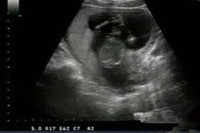

據(jù)說B超看胎兒性別是準(zhǔn)確率比較高的一種方式,那么,懷孕四個月的時候可以通過B超查看胎兒性別嗎?事實(shí)上,懷孕四個月的時候胎兒的生殖器官已經(jīng)形成,此時正是鑒別的最好時機(jī)。懷孕四...

懷孕三個月的胎兒性器官已經(jīng)慢慢發(fā)育成型,所以,這個時候利用B超來看男女是再合適不過的時間了。懷孕三個月男胎兒圖什么樣?懷孕三個月是男是女B超顯示上有何區(qū)別,一起來下文尋找答...